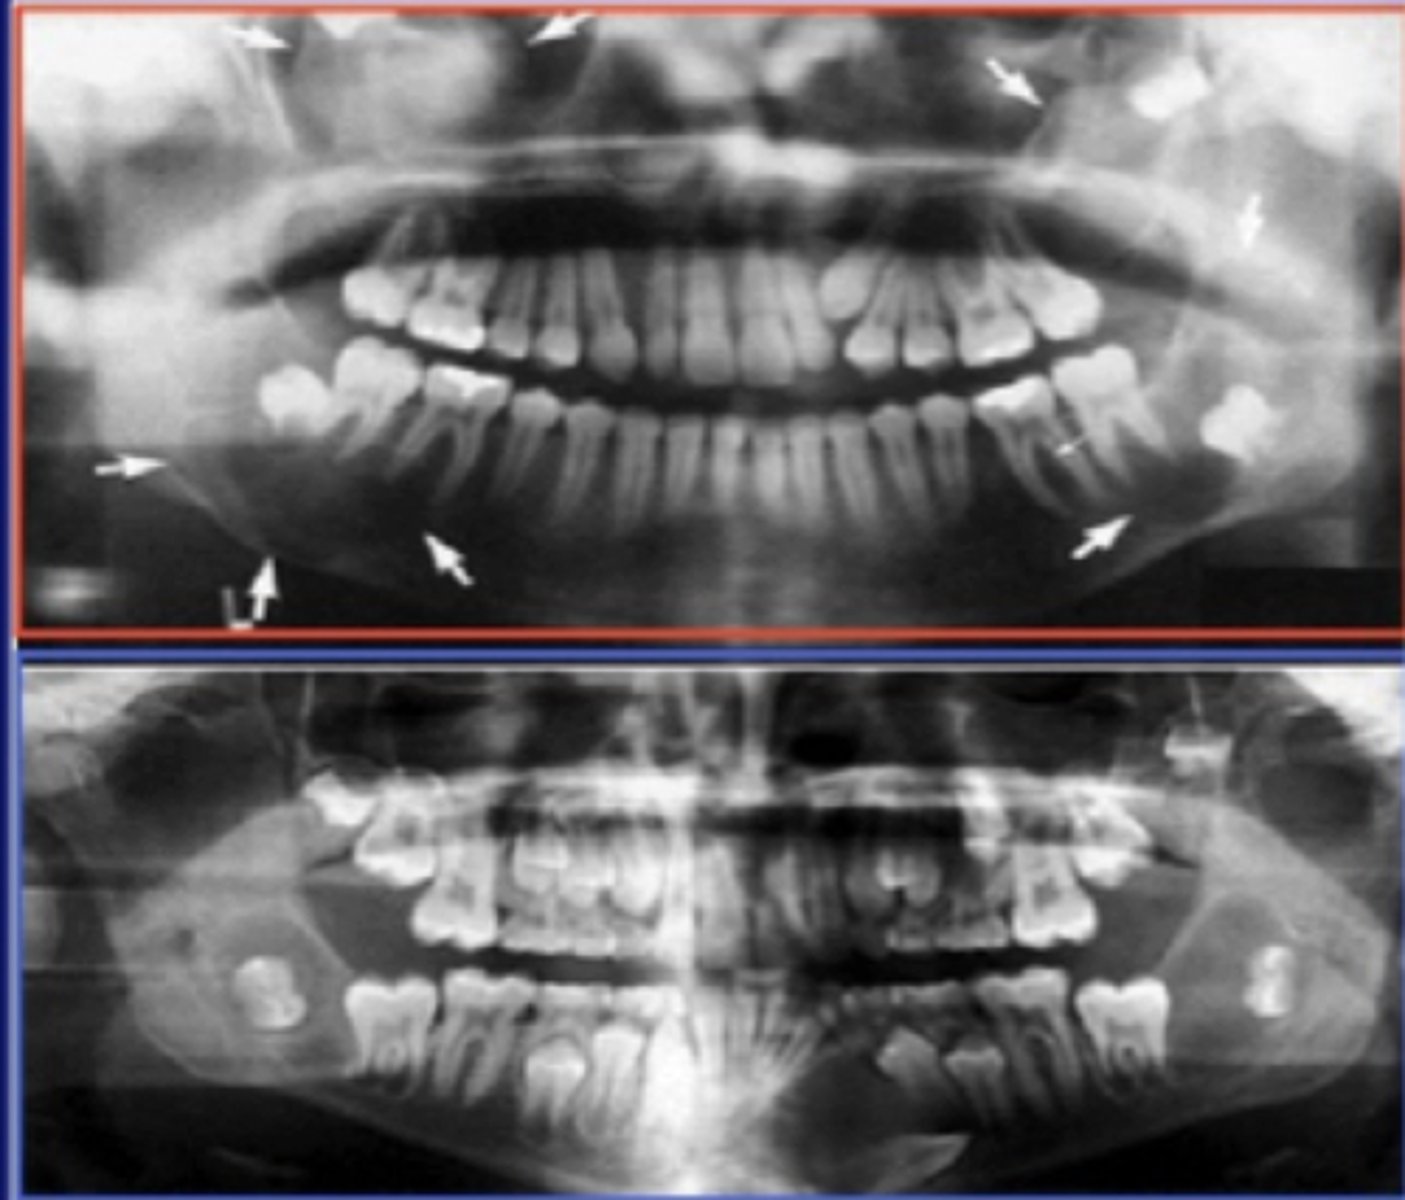

Characteristics of down syndrome include:

1. Slanted eyes

2. Shorter stature

3. Heart abnormalities

4. Varied intelligence levels

5. Fissured tongue

6. Hypodontia

7. Abnormally shaped teeth

8. Anomalies in eruption with malposition and crowding of teeth are common

Gingival and periodontal disease has been reported in _______ of affected individuals with down syndrome

90%